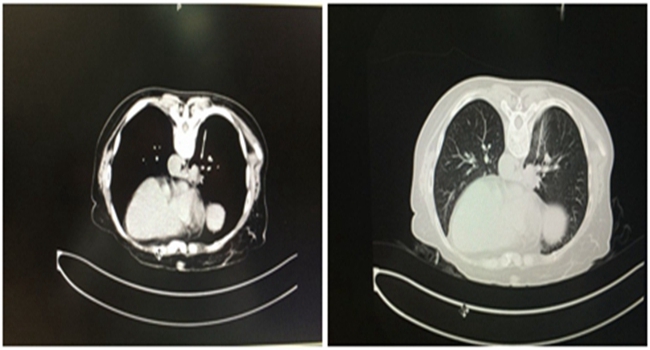

某患者于2016-04-19就诊我科,依据PET-CT检查,拟诊“右肺癌 多发骨转移癌”,患者剧烈疼痛,严重影响日常生活。在北京就诊半月余,因肺部肿块位置非常特殊,上面是下腔...